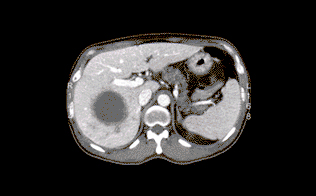

간농양은 그 발생 원인에 따라 화농성 간농양과 아메바성 간농양으로 분류하며 아메바성 간농양의 원인이 기생충인 Entamoeba histolytica인 반면 화농성 간농양은 세균이 원인이다. 발열 및 오한, 상복부 통증, 오심(구역질), 구토, 설사등의 임상 증상이 발생하며 황달이 발생할 수 있다. 화농성 간농양은 경피적 배액술과 항생제로 치료하며, 아메바성 간농양은 항아메바성 약물로 치료한다. 때로 수술이 필요할 수 있으며 적절히 치료된 경우 예후는 양호하다.